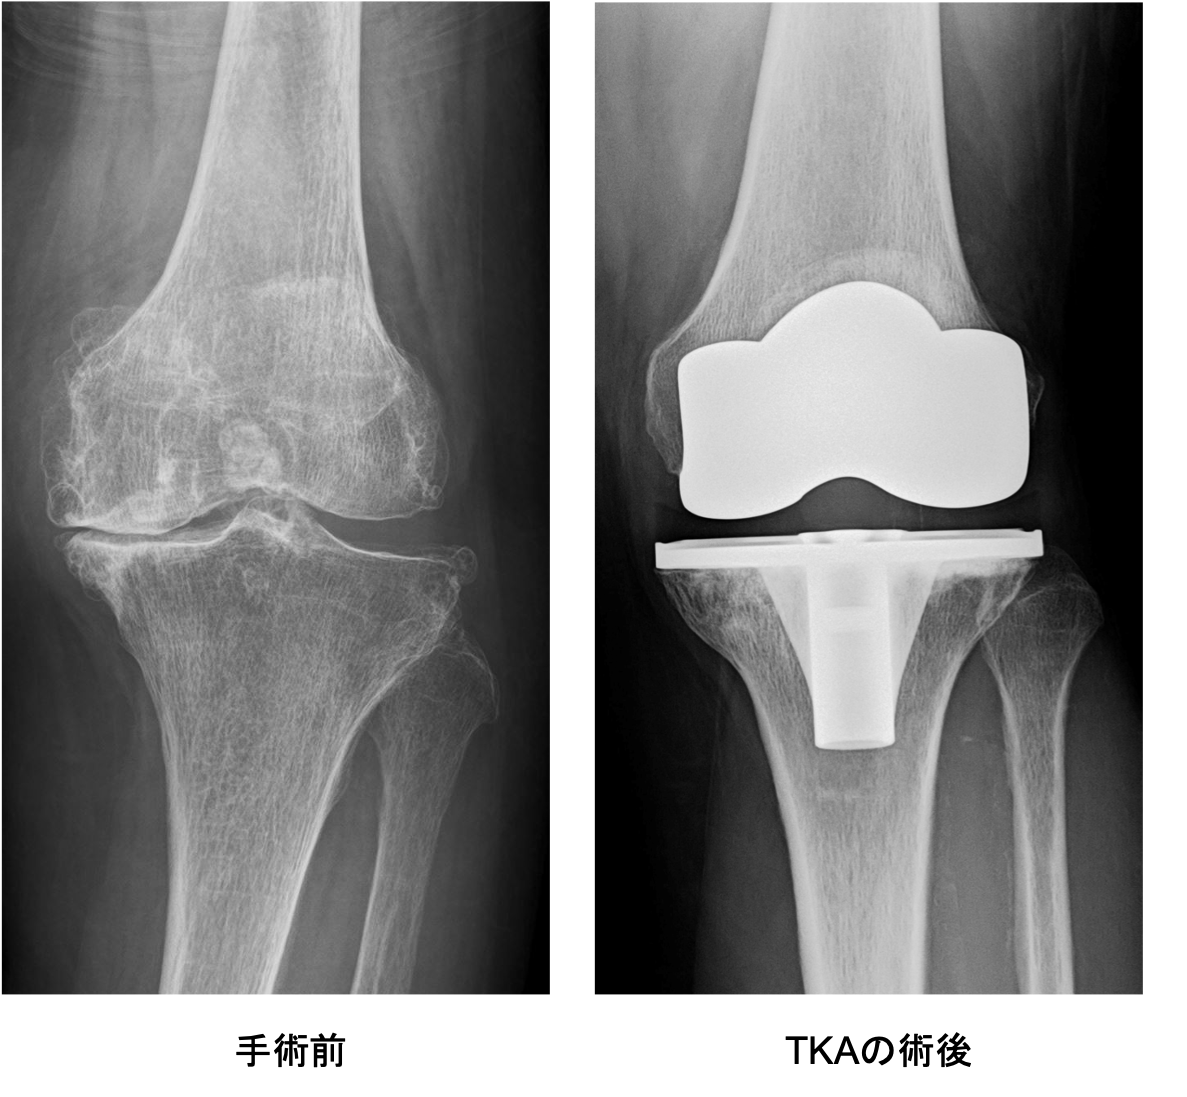

変形性膝関節症は一次性と原因疾患に続発する二次性に分類されます。わが国では年齢による退行性変化を主因とする一次性が多く、軟骨のすり減り、骨棘(骨のとげ)を伴い、多くは内反変形(O脚)を呈します。女性に多く、特に肥満との関連が強いといわれています。膝関節には歩行するだけで体重の3倍の力がかかるといわれており、病状の予防や進行を抑えるためには体重のコントロールが最も重要です。症状には波がありますが、次第に進行し、変形も悪化してきます。まずは保存加療を行いますが、痛みが強く日常生活に支障をきたすようだと、我慢するメリットはありません。痛みのない脚でより良い人生を送るために手術という選択肢もありますので、痛みで悩まれている場合は早めにご相談ください。

HTOの術後レントゲン

傷んだ関節表面を人工関節の形に合わせて削り、金属、セラミック、ポリエチレンでできた人工関節を骨の上に固定します。この手術を受けることで、関節の動きが滑らかになり、O脚やX脚といった変形が改善し、まっすぐな脚にすることが出来ます。人工関節の耐久性は10年間弛みなく日常生活が送れる可能性が95%以上といわれ、長期的にも安定した方法です。さらに最新の人工関節では性能が格段に良くなっており、20〜30年以上の機能することも十分期待できるようになってきました。

手術前

手術後